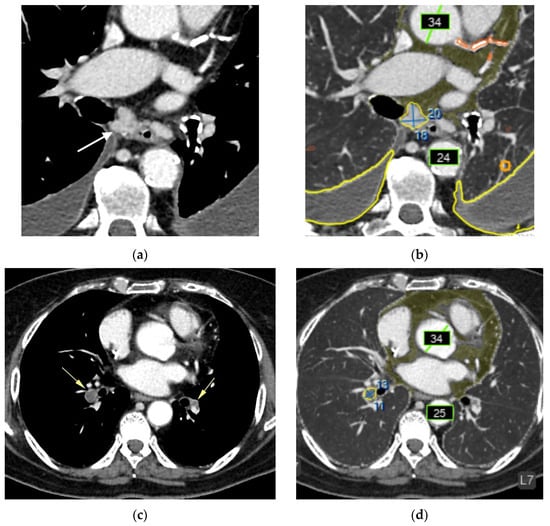

- Urolithiasis (1) (Figure 4).

- Adrenal thickening (10) (Figure 5).